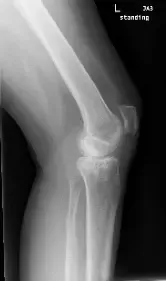

X-ray of a left knee

The patient was a 55 year old female presenting to the office with complaints of worsening left knee pain for the last three years. The patient was referred to us by one of our previous patients and was working as a guidance counselor in a school. The patient stated that she had sustained a slip and fall in 2017 fracturing her left upper leg. She was hospitalized and was treated with open reduction and internal fixation of the left lateral tibial plateau.

She subsequently resumed her activities but over the past year, started experiencing worsening left knee pain. The pain was described as sharp to dull ache with worsened on activities such as walking, climbing stairs, bending, kneeling and getting up from a chair.

The pain has recently been disturbing her sleep. She stated she was under tremendous emotional stress due to pain in her daily activities.

She had restricted her activities due to pain and tried conservative management in the form of physical therapy, cortisone injections, braces, and heat pads but with minimal relief.

The patient was a former smoker having quit ten years ago and had comorbidities of hypothyroidism and hypertension. She is currently using a cane as a walking aid.

On physical examination, she demonstrated tenderness on the medial joint line and medial patellar facet. She was uncomfortable with the examination due to pain. After a thorough evaluation and imaging studies, she was advised about the hardware removal from the lateral tibial plateau with subsequent total knee replacement using custom implants and instruments.

Imaging studies revealed tricompartmental osteoarthritis, most severely affecting the medial compartment with a post-traumatic deformity of the proximal tibia.